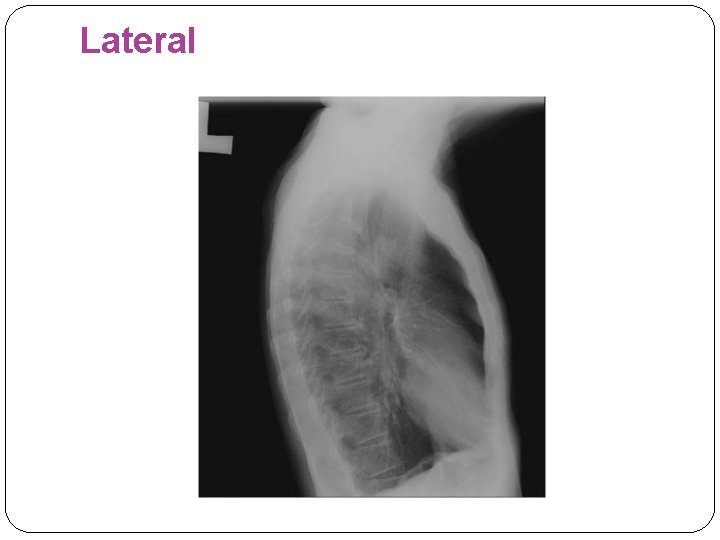

Lateral